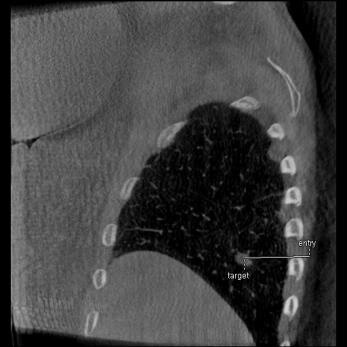

Planifier